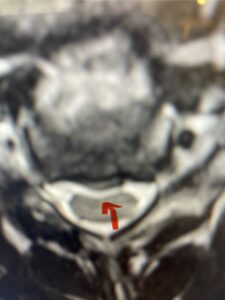

In this next case, this patient is a 47 year-old female who presents with intractable low back pain with severe pain, numbness, and weakness in the right lower extremity that had gotten progressively worse over a year. The patient had failed conservative management including physical therapy and epidurals. She was noted to have ⅘ weakness of plantar flexion. MRI demonstrated a large right L5-S1 disc herniation with severe compression of the descending right S1 nerve root (Fig 3). It was decided to perform a right L5-S1 hemilaminectomy for removal of the disc fragment and decompress the S1 nerve root. When you expose the disc, one must be certain to release any anterior adhesions to the nerve root in order to prevent a dural tear during retraction of the nerve root. It is also important to make sure during exposure and you finally encounter the dura after removing the ligamentum and fat, to make sure you are looking at the nerve root and not the main trunk of the thecal sac because if you don’t you can avulse or damage the nerve root if you retract the wrong structure.

Fig. 3a: Sagittal and axial T2-weighted lumbar MRI images demonstrating large right L5-S1 disc herniation (red arrows)

We found a massive subligamentous herniation which had to be revealed by having your partner retract the freed nerve root with a nerve root retractor and putting slight downward pressure on the more medial and anterior disc space. There is nothing more satisfying when the jelly (disc fragment) of the annulus (donut) comes squirting out and you remove a large chunk of disc material that clearly was stretching the ligament membrane and compressing the nerve root. This does cause back pain in addition to radiculopathy not only by the component of mechanical compression but also the stretching of the nerves within the ligament. We performed this surgery and noted that the nerve root was a very angry red color or hyperemic and we removed a large subligamentous fragment. The patient had improvement of her preoperative radicular symptoms.